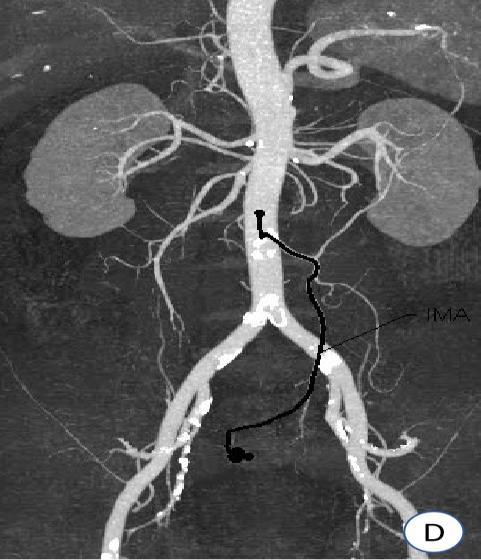

• 计算机体层摄影血管造影在腹腔镜结肠癌根治术前评估中的应用效果

摘要:目的 分析计算机体层摄影血管造影(CTA)在腹腔镜结肠癌根治术前评估中的应用效果。方法 回顾性分析2021年1月-2024年2月于该院接受腹腔镜结肠癌根治术的120例患者的临床资料。其中,60例行常规腹部CT和CTA,60例行磁共振成像(MRI)。以术后病理为金标准,判断CTA对临床T分期与术后病理的一致性,以及评估肿瘤是否侵犯肠系膜血管和周围组织的准确度。结果 术前CTA诊断T分期的准确率为95.00%(57/60),一致性好(Kappa = 0.925,P < 0.05);术前MRI诊断结肠癌T分期的准确率为98.33%(59/60),两者比较,差异无统计学意义(χ2 = 0.26,P > 0.05)。CTA预判肿瘤是否累及肠系膜上动脉、肠系膜上静脉、肠系膜下动脉、肠系膜下静脉、腹主动脉、肾动脉、肾静脉和脾动脉等血管,与术后病理的一致性好。特别是在预测肠系膜血管受累方面,CTA的敏感度为94.44%,特异度为95.83%,准确度高达95.00%。结论 对于行腹腔镜结肠癌根治术的患者,术前CTA不仅能清晰地显示结肠癌T分期,还能揭示肠系膜血管的走行和变异,以及肿瘤与周围组织的关系和侵犯程度,从而为手术规划提供强有力的支持,确保了腹腔镜手术的安全性,减少了不必要的手术风险。